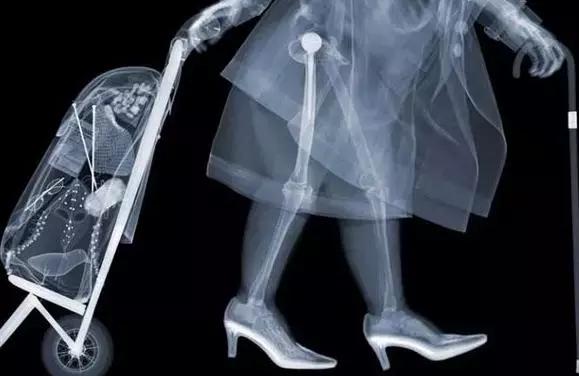

X射线

把蛋糕压扁检查

原理:X光穿过人体,不同部位吸收射线,底片上不会曝光或部分曝光,洗片后这个部位就是白色的。

优点:快捷、价廉。

缺点:受制于深浅组织的影像互相重叠和隐藏,有时需要多次多角度拍摄X光片才能看清。

X射线是著名的伦琴发现的,它是影响医学的开端。X线发明的故事大家也都熟悉,伦琴在一个偶然的机会下从X射线现中看见了自己手的骨骼,所以说X射线主要是用来看骨头。

此外还有一个最常见的作用是拍胸片,主要是粗略的看一下肺部和心脏的轮廓,诸如肺部感染、先天性心脏病导致的心脏大小形态变化、肺癌之类的典型的影像表现,x片能够做到一目了然。